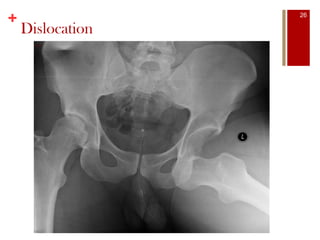

Dislocation

26

• #27 Relatively uncommon during athletics due to the thick capsule